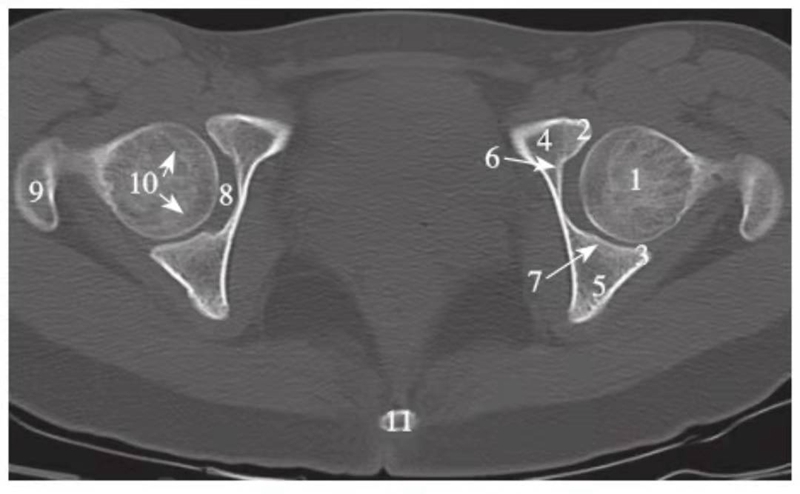

图4 股骨头凹下方层面(骨窗)

1.股骨头;2.髋臼前唇;3.髋臼后唇;4.前柱;5.后柱;6.髋臼前壁;7.髋臼后壁;8.髋臼窝;9.大转子;10.股骨头骨骺线;11.尾骨